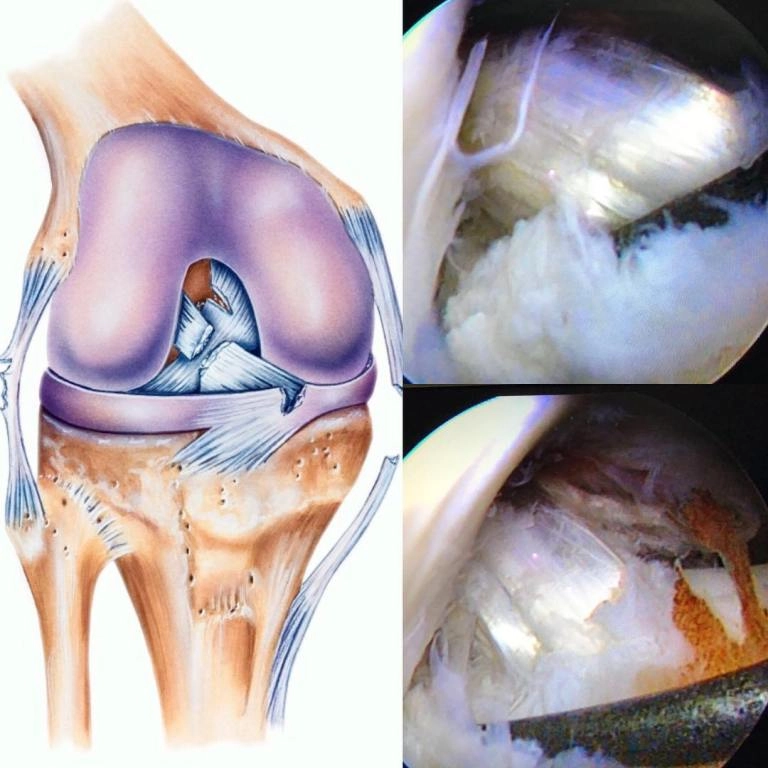

Рамазанов Гаджимурад Магомедович. Травматолог-ортопед. Артроскопия. Мениск. verified